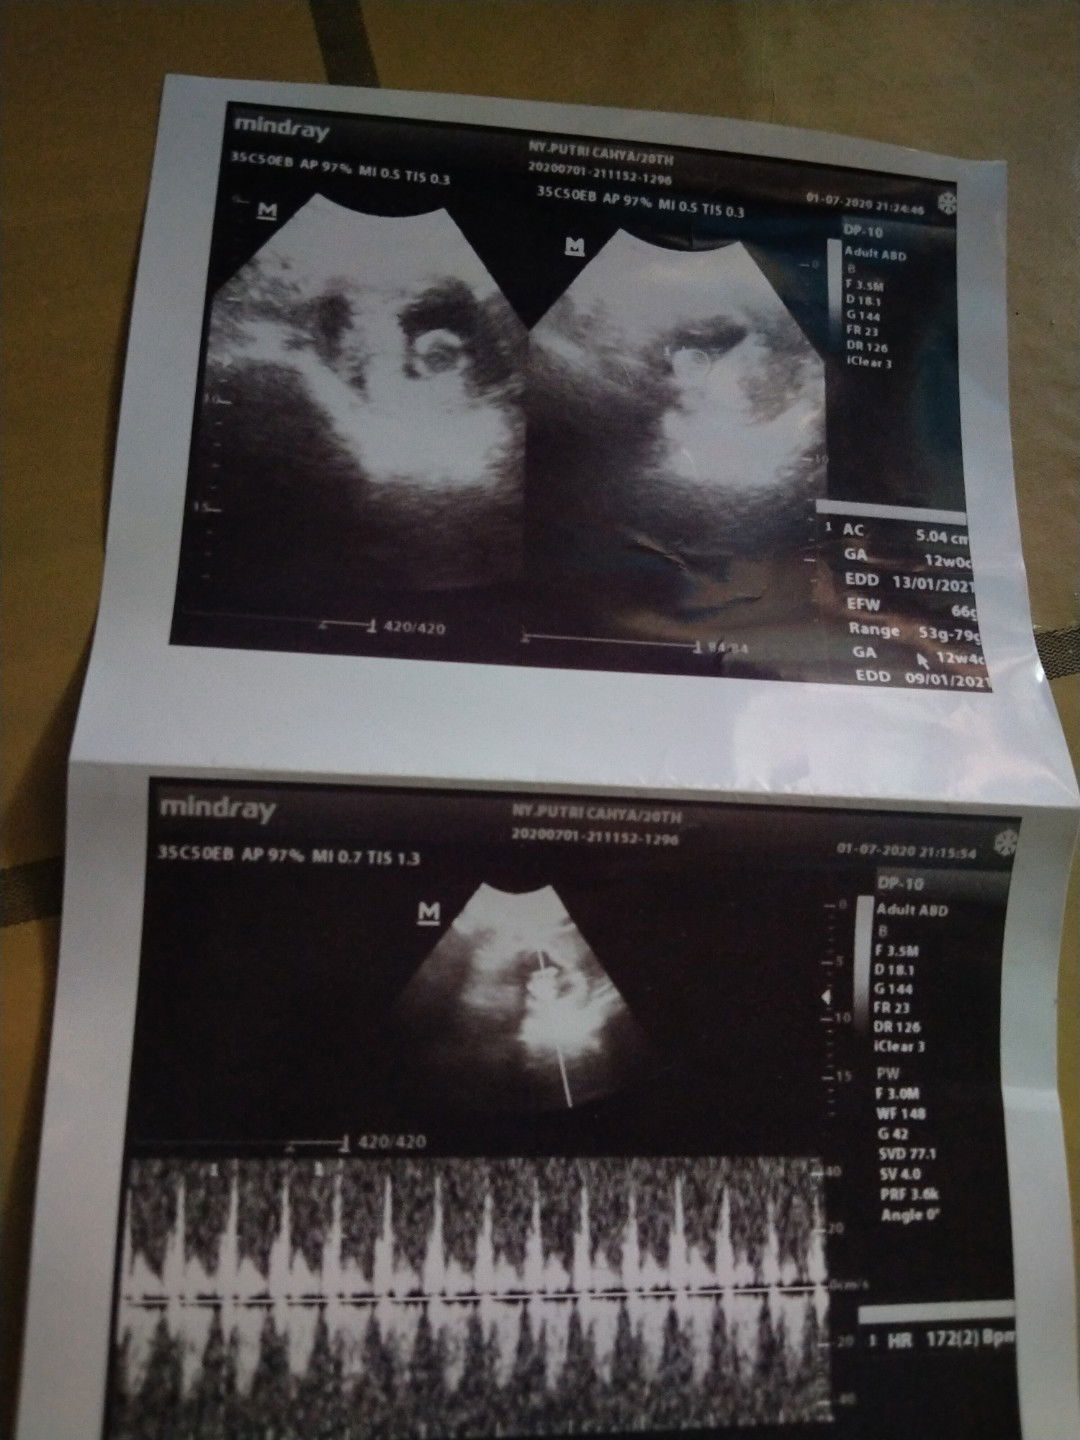

Bun mau tanya,tlong lolosin ya.. saya kan hpht 13maret 2020. Perhitungan aplikasi dan usg saya baru hamil 15week 5hari, tpi tadi saya posyandu kata bidannya diraba kok belum terasa dan saya di saranin buat usg, pdhal saya udh usg tgl 1 juli kemaren.. dan perkiraan bidan saya udh 4 bulan lebih 8 hari.. yg bner yg mana ya bun hitungannya? Dan apa kalo 4 bulan blum trlalu trasa itu wajar ? Saya jadi bimbang pdhal jelas2 udh usg dan baby nya sehat, tp kok bidannya bilang gtu saya jdi sedihndan kfikiran.. masak iya saya harus usg lagi😣 dan ini hasil usg saya tgl. Kmaren.. dan menurut prhitungan bunda2 bner yg mana

Bun mau tanya,tlong lolosin ya.. saya kan hpht 13maret 2020. Perhitungan aplikasi dan usg saya baru hamil 15week 5hari, tpi tadi saya posyandu kata bidannya diraba kok belum terasa dan saya di saranin buat usg, pdhal saya udh usg tgl 1 juli kemaren.. dan perkiraan bidan saya udh 4 bulan lebih 8 hari.. yg bner yg mana ya bun hitungannya? Dan apa kalo 4 bulan blum trlalu trasa itu wajar ? Saya jadi bimbang pdhal jelas2 udh usg dan baby nya sehat, tp kok bidannya bilang gtu saya jdi sedihndan kfikiran.. masak iya saya harus usg lagi😣 dan ini hasil usg saya tgl 1 Kmaren.. dan menurut prhitungan bunda2 bner yg mana?